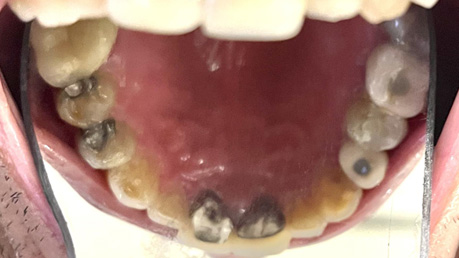

Patient Intraoral Photographs

- Mandible